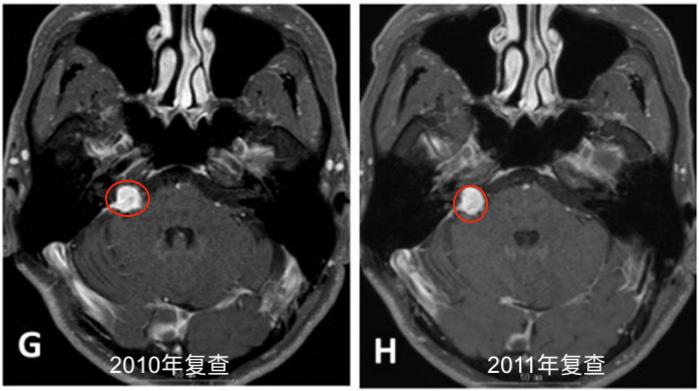

G. 2010年11月轴位钆剂(Gd)增强T1加权MR图像。H. 2011年11月随访的轴位钆剂(Gd)增强T1加权MR图像。I.2012年11月随访的轴位钆剂(Gd)增强T1加权MR图像。J. 2013年11月随访的轴位钆剂(Gd)增强T1加权MR图像,显示肿瘤开始生长。

2004年5月,采取右侧乙状窦后入路切除肿瘤。术中肿瘤质地坚实(solid),血管相对丰富,易出血,部分切除肿瘤(图1A-B),于2005年8月行伽玛刀放射外科治疗(GKS)(图2)以控制当时的残留肿留。2007年5月行第二次手术切除,因蛛网膜边缘不清,与面听神经和后组颅神经粘连严重,残留部分肿瘤囊壁(图1C-D)。病人每6个月定期随访脑部MRI(图1E-I),最初的残留肿瘤的大小是稳定的。2013年11月,常规随访MRI显示肿瘤开始生长(图1J)。2014年4月出现进行性头痛、眩晕、和恶心,MRI显示肿瘤肿块增大。2014年6月(图1K-L)进行次全肿瘤切除,术中发现显示,肿瘤有两个部分,也就是说,有一部分是软的且相对容易切除,另一部分有弹性伴有纤维组织,蛛网膜边界不清楚,与面听神经和后组颅神经严重粘连。本病例的第二次及第三次手术均由同一位神经外科医生完成。